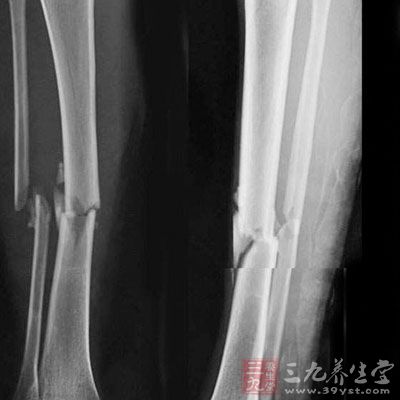

JCO造血干细胞移植增加骨折发生率